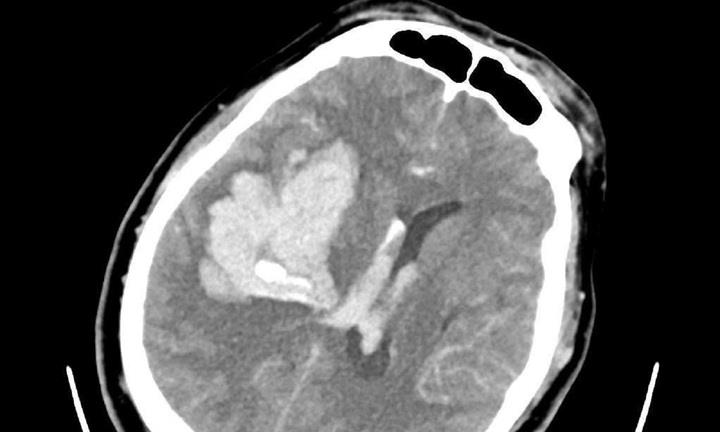

Cụ bà 75 tuổi bất ngờ lên cơn đột quỵ sau khi thức dậy đi vệ sinh lúc 2h sáng, với các triệu chứng méo miệng, chóng mặt, tê bì nửa người trái và mất thăng bằng.